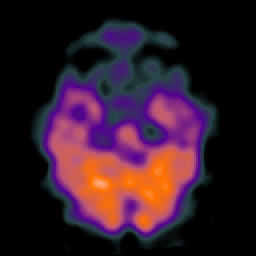

Alzheimer's Disease: SPECT/fMRI overlay -- Slice #2

[Home][Help][Clinical] Slice 2